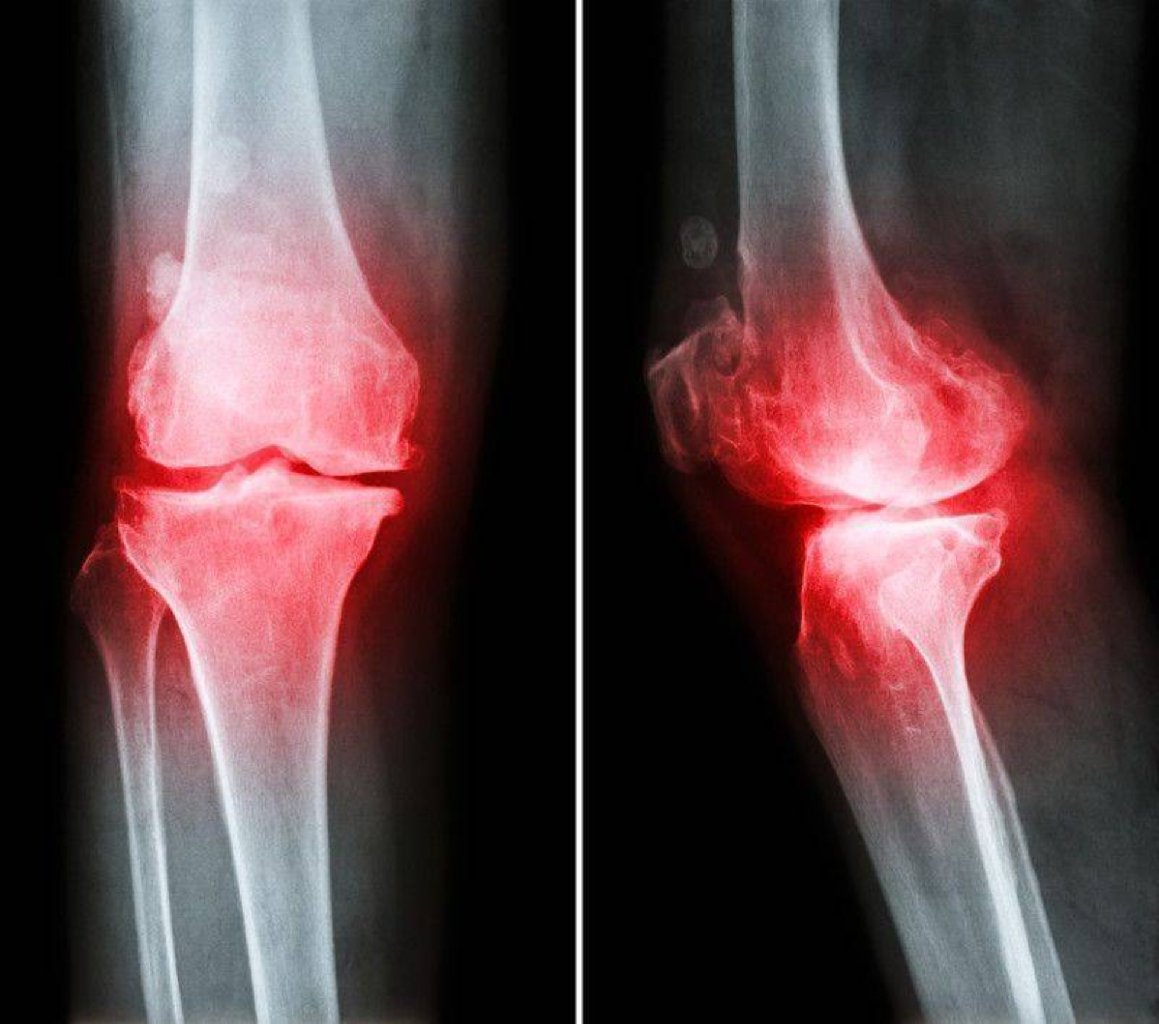

Simptomlar: Ağrı: Xüsusilə hərəkətlə artan oynaqlarda ağrı. Ağrı əvvəlcə fəaliyyətlərlə artsa da, xə ...

Belirtiler Osteoartritin belirtileri arasında şunlar yer alır: Eklem ağrısı, özellikle hareket ...